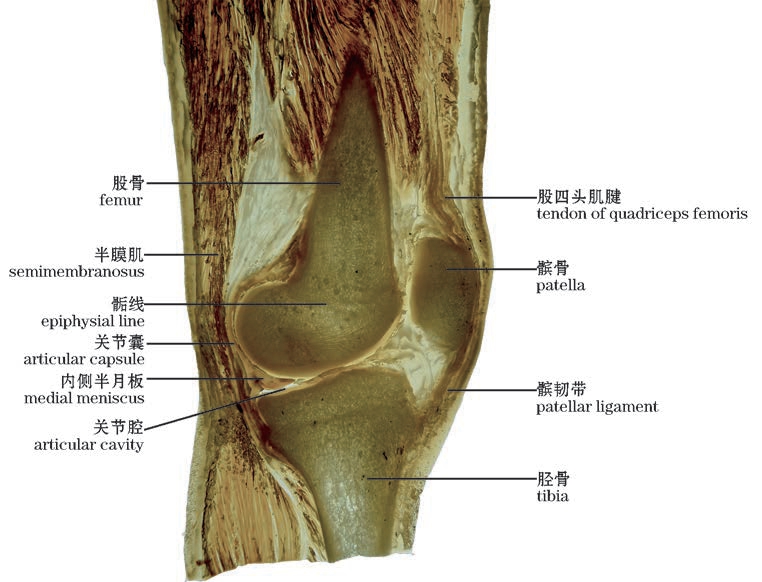

图2-48(1) 膝关节矢状切面—1

The knee joint.Sagittal section—1

img

图2-48(2) 膝关节矢状切面—2(外侧面观,左)

The knee joint.Sagittal section—2(Lateral view,left)